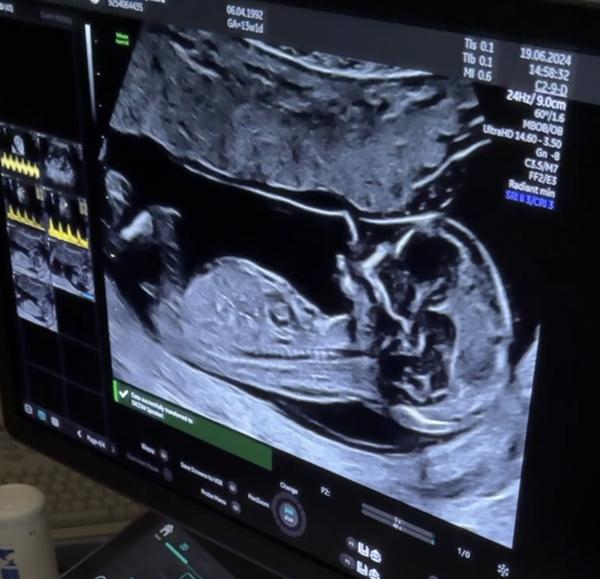

prosím, jaké je pohlaví miminka na fotce?

Je to ultrazvuk z 13+1.

ve 13. týdnu jsou odhady, jak házení korunou, ale o něco pravděpodobnější je chlapeček. Určitě ale vyčkejte na potvrzení později během screeningu ve 20. týdnu, než budete nakupovat a malovat. 🙂